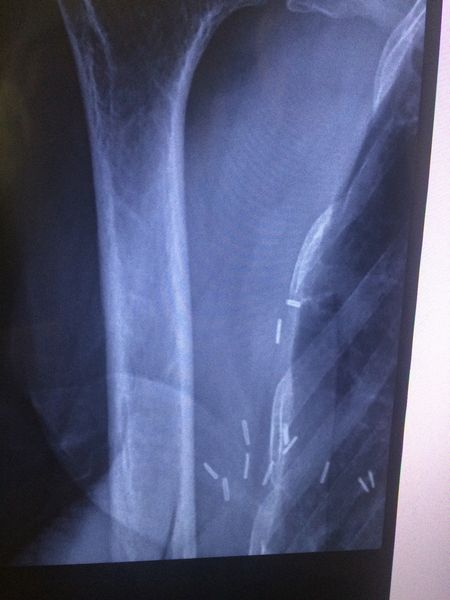

@Afraser, my point exactly.....it's not that they were used, it's that I was not told that they were used and will remain there. Titanium appears to be a safe option, that the older version had nickle as well, which caused problems in some. However, there is a small population of patients who can, in fact have an allergy to titanium, specifically those with autoimmune problems which put them at risk of their bodies over reacting to what, in others, would be seen as no threat by their bodies. That is, an inert substance not worthy of getting excited about. In my case, by body goes apeshit over essentially nothing, as a matter of course. I have scleroderma, Sjogren's Syndrome,and antiphospholipid antigen syndrome, as well as positive antibodies to lupus. All autoimmune diseases. I just feel that a heads up would have been appropriate, so that if at some point in the future, I manifested signs of some sort of allergy or whatever, it would have been on my radar that the clips might potentially be a cause.